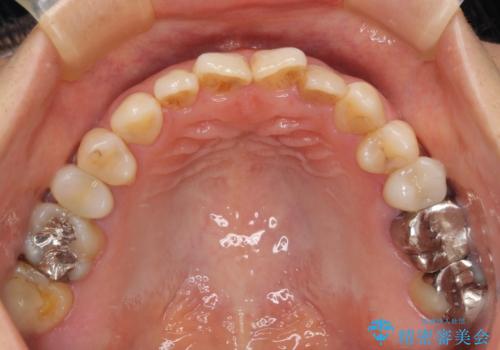

- 前歯に痛みを感じて来院された患者様です。

以前虫歯治療を行った歯が痛み出し、鼻の下を押すと強い痛みを感じていました。

レントゲン写真から、大きくなった根尖病変が認められました。

根管治療を行い、その後オールセラミッククラウンにて補綴治療を行うこととしました。